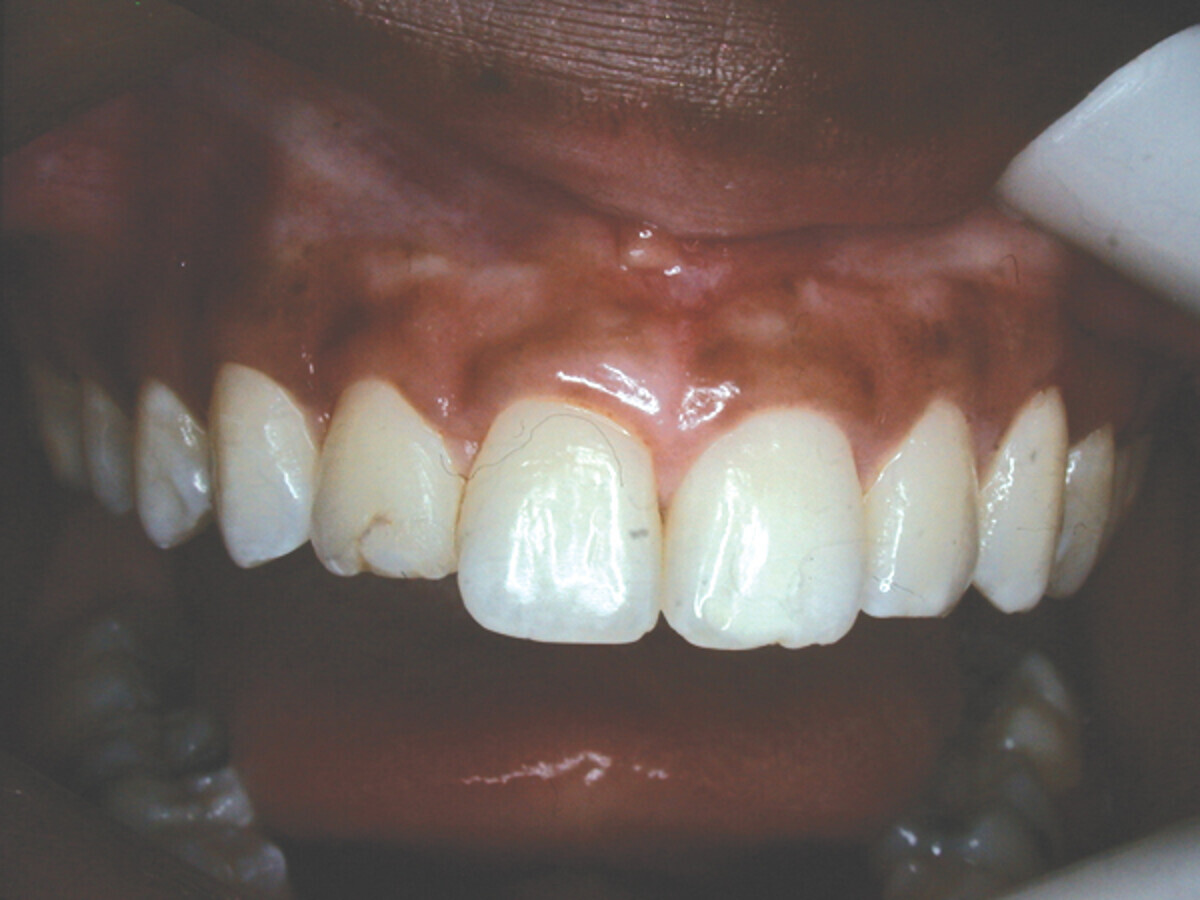

In this example case, a 19-year-old woman wanted a beautiful smile she could be proud of (Fig. 1). Initially, she presented with bleeding gingiva, but after a series of non-surgical treatments, which included oral hygiene instruction, the bleeding ceased.

Her #7 appeared to not look clean, with a worn, stained restoration labially. It also appeared short in height. The centrals had a square appearance, not the length of a normal appearing incisor, but shorter and not streamlined. The cervical line was irregular, the cuspids being higher and the centrals irregular and lower.

Fig. 1: Before, patient wanted a nicer smile. (Photo: Dr. David L. Hoexter)